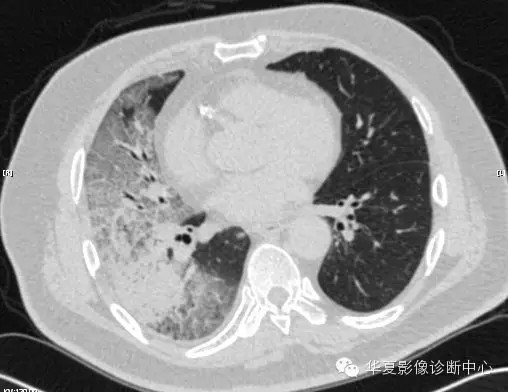

【病例学习】甲型H7N9禽流感一例

男性 63

发热咳嗽5天

2013-4-5拍片示右肺实变,收入院,追问病史,发病期间肌肉酸痛,头痛,无腹痛腹泻,无明显胸闷气急,无意识改变。有高血压病史,无其它病史。

2013-4-7CT进一步检查。

最终诊断:H7N9。